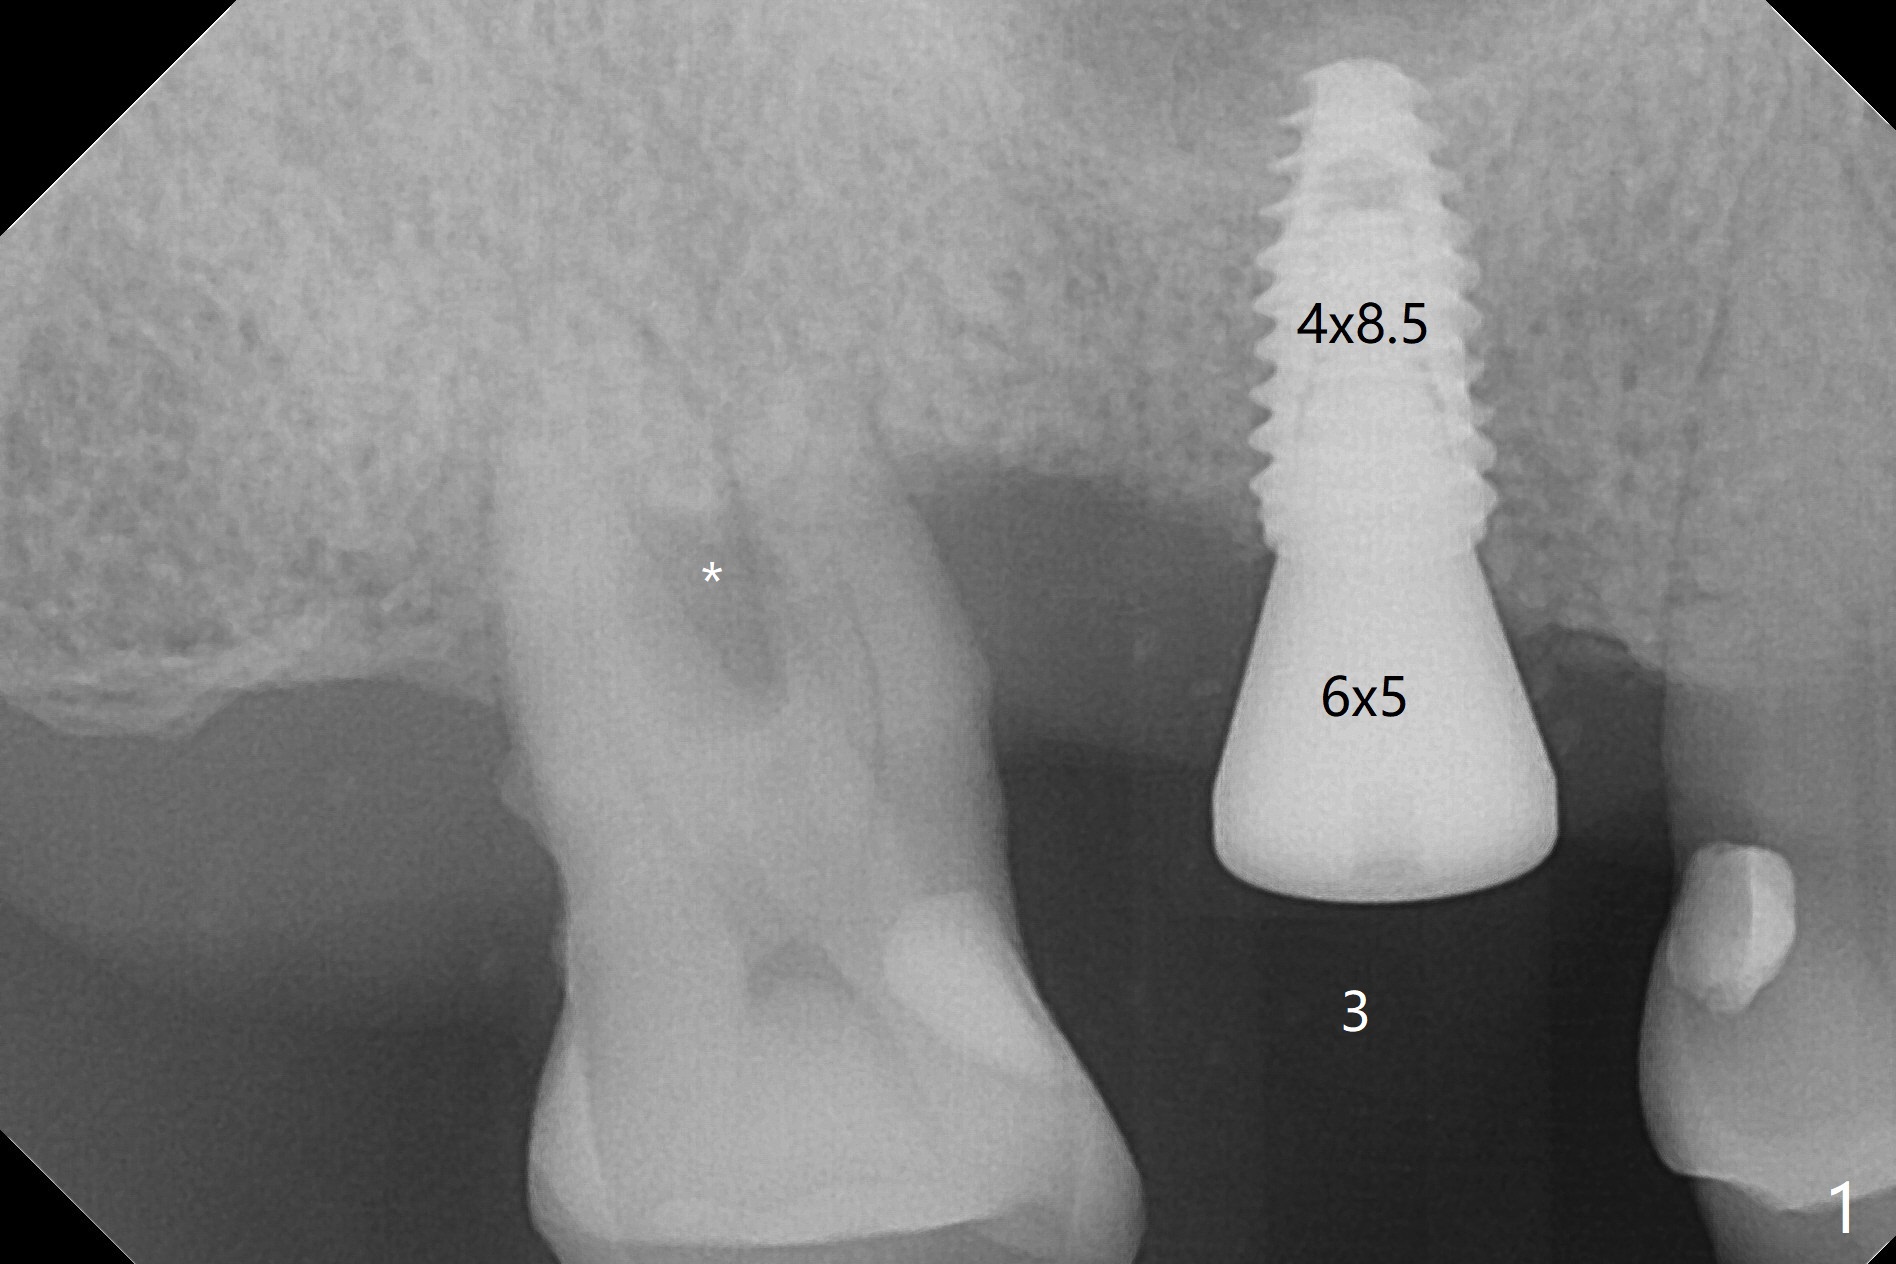

当3号牙短小植体植入后(图一(骨质密度高)),病人纳闷为什么不给他装临时牙冠,术后两个月又打电话要求提前修复,因为放置愈合基台,他无法使用局部托牙(单个牙),而14号牙即刻植牙即刻修复。他无法理解我们苦衷,有什么补救方法?

使用来自钻头的自体骨做提升,植体植入后,颊侧骨板薄,刚好骨下。使用5.5毫米profile drill后,放置愈合基台,术后三个月脱落,他再次要求修复,甚至提出退款,不愿意回诊所,因为他有糖尿病,新冠病毒高危人群。 放置小号愈合基台(图二)。他原来托牙是Valplast,没有occlusal rests,不能经过修改临时使用,可能将直接放置修复基台做临时牙冠。放置修复基台后(图三(术后三个月)),制作临时牙冠时,发现前者有些松动,后者就没有粘固。当基台完全就位,它最冠方与植体没有间隙(箭头),根方有间隙(空心箭头)。其实愈合基台也是一样(图一,二)。后来植体松动(术后4个月),拔除,植骨(图四),颊侧骨板缺失(图五:B)。植骨后5个月2号牙疼痛需要拔除种植(图七),与3号牙一起种植(图六),颊侧骨板修复,但是高度有所下降(箭头)。The narrow ridge with the intact buccal plate (Fig.8 >) can hold a 4x8.5 mm implant. The buccal plate is lost 4 months postop (Fig.9) and restores 5 months post graft (Fig.10). Return to Upper Molar Immediate Implant, No Deviation Coronal and Apical Gap in IBS implant Protect Graft Xin Wei, DDS, PhD, MS 1st edition 06/22/2020, last revision 05/02/2021